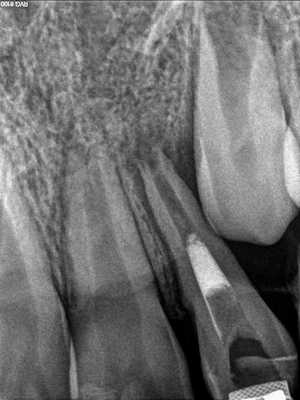

Фото 3. Рентгенограмма, демонстрирующая пример резорбции по причине давления.

В течение последних двух десятилетий в стоматологической литературе была представлено значительное количество публикаций, описывающих уникальные случаи внешней резорбции полностью витальных зубов в области шейки. Следовательно, данную разновидность патологии пришлось добавить к двум уже ранее известным (фото 4). Иногда термины для описания данного вида поражения носят лишь субъективный характер, но для четкого понимания в данной статье будет использоваться название инвазивная пришеечная резорбция корня (ИПРК), поскольку именно такое название данной патологии дал доктор Geoffrey S. Heithersay, который и описал ее первично. В данной статье будет рассмотрены как клинические, так и рентгенологические признаки резорбции, а также аспекты, связанные с ее этиологией, патофизиологией и лечением.

Фото 4. Рентгенограмма, демонстрирующая пример инвазивной пришеечной резорбции.